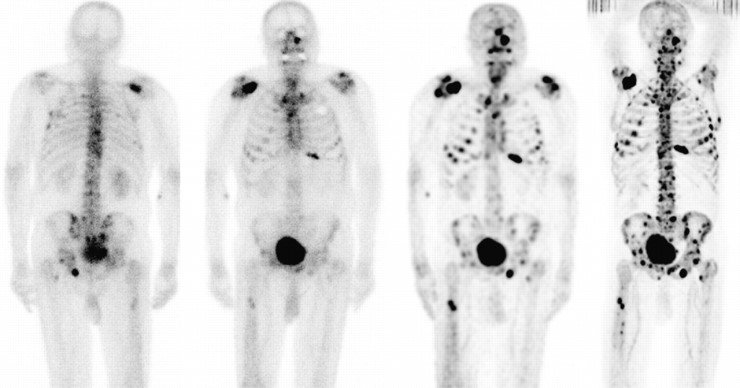

유방은 남녀 모두 있지만 여성의 유방은 사춘기부터 발달하고 각종 호르몬 작용과 모유를 생산하는 기능을 합니다.이런 여성의 유방에서 암세포가 발생한 것을 유방 암이라고 합니다유방 암의 원인에는 여성 호르몬 문제나 방사선의 많은 노출 외에도 식사 습관, 흡연 음주 환경 호르몬 등의 위험 요인으로 보고됐고, 가족력이 높은 유방 암 발병률을 나타내는 유전적 요소도 크게 작용하는 것으로 보고되고 있습니다.유방 암은 1기에는 90~100%정도의 높은 생존율을 보이지만, 유방 암 말기의 4기는 20~30%의 매우 낮은 생존율이라고 보고되어 생명을 위협하게 됩니다.유방 암 말기는 유방의 암세포가 다른 장기로 전이된 상태를 의미합니다만, 유방 암의 골 전이 증상으로 유방 암의 간질/유방 암의 간질 전이, 유방 암 폐 전이까지 다른 장기로의 전이가 발생하는 경우가 많고, 무기 관리가 매우 중요합니다.오늘은 유방 암의 골 전이 증상으로 유방 암 줄기 전이 증상 등 전이에 따른 증세와 유방 암 말기 등 예후를 높이기 위한 소재까지 소개합니다.

유방 암의 초기에는 아무런 증상도 없이 우연의 검진과 유방 암 말기로 이어질 때 뚜렷한 증상이 발생하는 것도 있지만 대표적으로 응어리가 닿거나 유두 분비물/젖꼭지의 고치기 어렵게 습진의 모습도 나타날 수 있습니다.유방 암 말기 증세로 유두가 유방의 안쪽에 침울한 증상이나 통증 체중 감소 등의 발생이 있습니다유방 암은 전이 부위에 의해서 생존율과 증상이 달라질 수 있습니다유방 암의 골 전이 증상의 경우 뼈가 척추를 누르고 통증과 행동 제한이 생긴다, 뼈가 약해지고 골절 하고 부러질 유방 암의 골 전이 증상이 나타날 수 있습니다.유방 암 폐 전이의 경우 호흡 곤란 및 각혈, 기침, 폐 출혈 등의 유방 암 폐 전이 증상이 있습니다.유방 암 튀김의 경우는 두통이나 인지 저하, 근육 경직 난청이나 경련 구역 구토 등의 유방 암 튀김의 증세가 있어요 마지막으로 유방 암 줄기 전이에는 발열과 무기력, 식욕 부진, 체중 감소, 드문 간이 커지고 복부 팽창 등의 유방 암 줄기 전이 증상이 발생할 수 있습니다.유방 암의 재발률은 20~30%에 해당하는 만큼 초기 발견에도 유방 암의 재발에 의해서 여러 장기 몸에 대한 전이가 발생하고 높은 무기에 진행되고 생명을 위협하는 것도 있습니다.그러나 반대로 유방 암 말기 유방 암이 다른 곳으로 전이된 상태에서도 완치하는 사례도 잘 있어 환자의 재발과 전이 등을 관리의 정기적인 추적 관찰과 향후의 병기 개선을 위한 예후 관리가 중요합니다 많은 예후에 대해서 음식이 있었는데 이곳에서는 많은 논문을 통해서 세계적으로 주목 받고 있는 말굽 버섯을 준비했습니다.